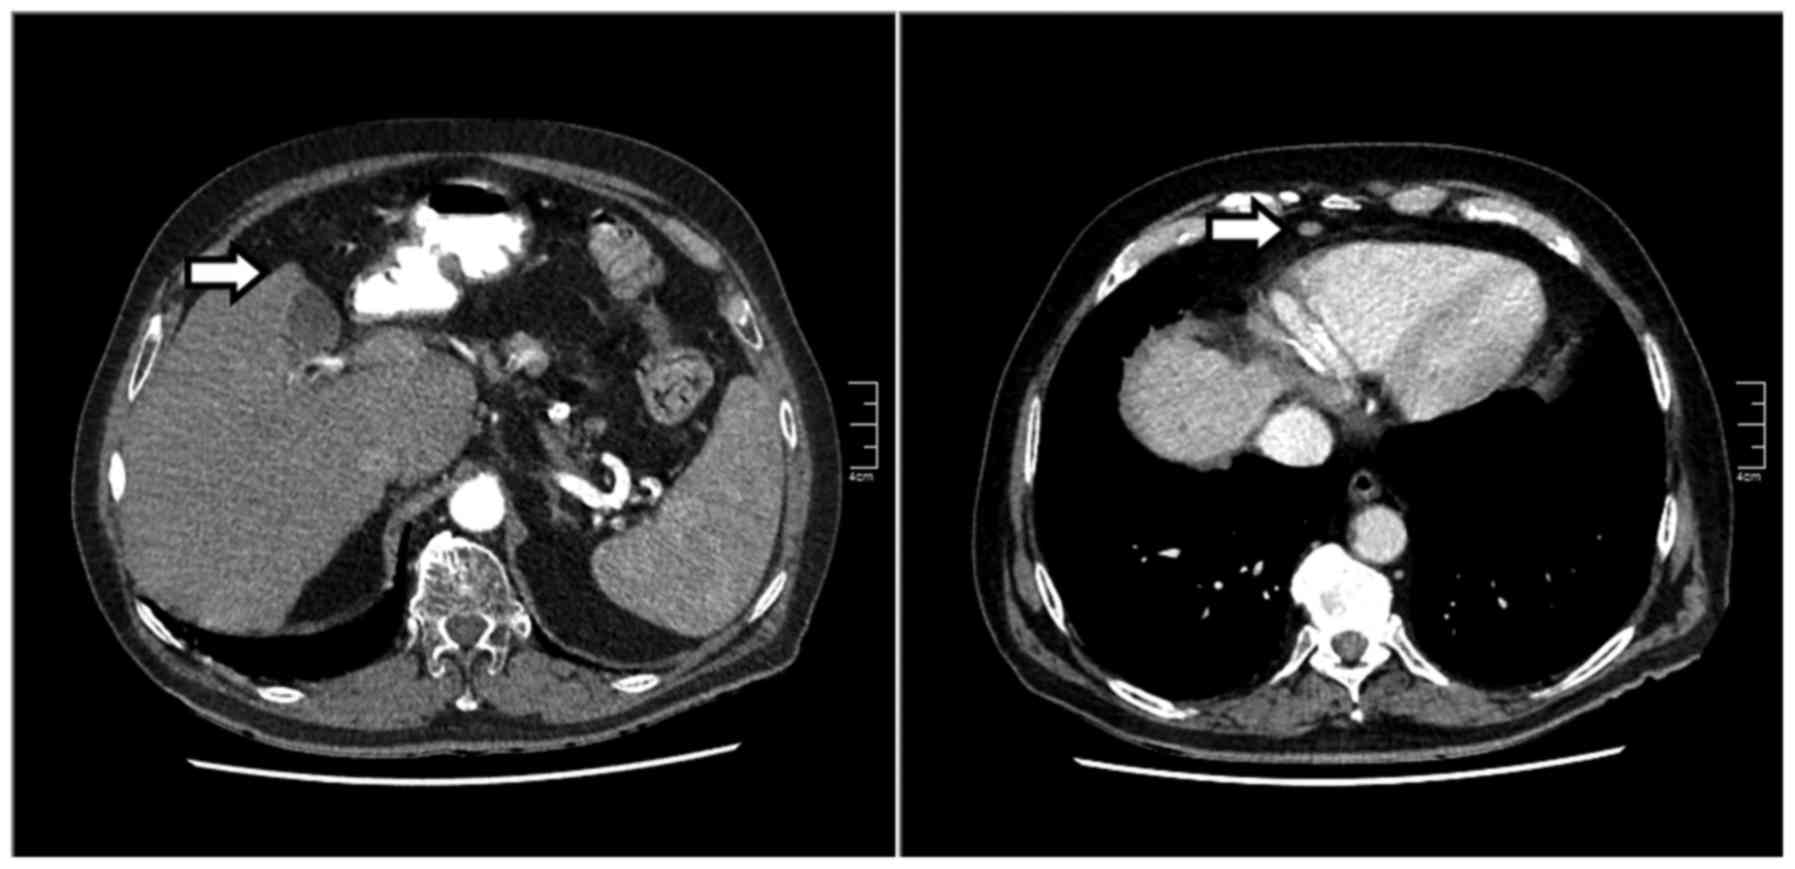

Six months later, the patient attended the outpatient clinic for re-evaluation of his disease. Over that time he had suffered a cerebrovascular accident (CVA) with ensuing partial hemiparesis. The AFP level had decreased to 1,795 kU/l. The CT scan revealed that the pulmonary lesion had disappeared, whereas the suspicious hepatic lesion and the lesion anterior to the pericardium had significantly decreased in size (Fig. 2). An ultrasound-guided biopsy was repeated and the pathological examination indicated the previously diagnosed HCC. An independent academic pathology department confirmed the results. The patient had gained 4 kg in weight over 6 months and maintained the consumption of 2 units of alcohol per day; he also reported improvement of his overall condition on a weekly basis. Two months after the CVA, he had been initiated on enalapril, furosemide and cucurmin, whereas he discontinued the use of simvastatin due to the side effects. The patient had not used androgens or herbal preparations and did not suffer from any type of inflammatory disease. One month later, the AFP level further decreased to 1,252 kU/l (Fig. 3).

Figure 2.

Follow-up computed tomography images at 6 months after initial diagnosis. The liver had significantly decreased in size. The suspicious hepatic lesion and the lesion anterior to the pericardium had also significantly decreased in size (arrows).